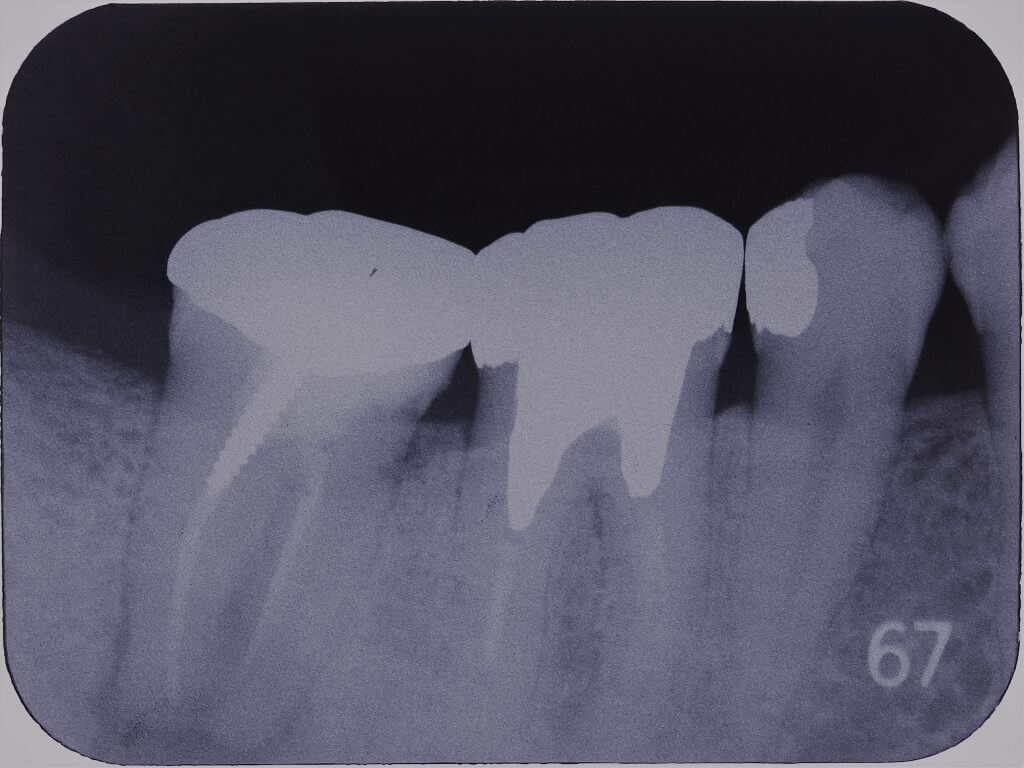

デンタル撮影でも根尖部に透過像があります。

根管充填はされてはいますがやや根管拡大と根管充填の質が低いように感じました。

またもしかすると樋状根になっているのかもしれません。